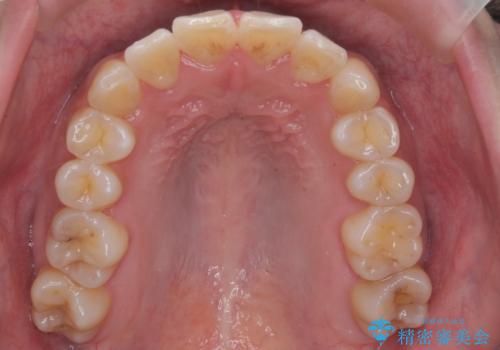

前歯のがたつきをなおしたい マウスピース矯正

担当医 大元洋佑

![[ マウスピース矯正 ] 前歯の角度・がたつきを治したい。の症例 治療前](https://seimitsushinbi.jp/wp/wp-content/uploads/2024/02/IMG_7820-500x350.jpg?v=1707810350)

![[ マウスピース矯正 ] 前歯の角度・がたつきを治したい。の症例 治療後](https://seimitsushinbi.jp/wp/wp-content/uploads/2024/02/8334681fa61954fc45ff8cef14f33166-500x350.jpg?v=1707810480)